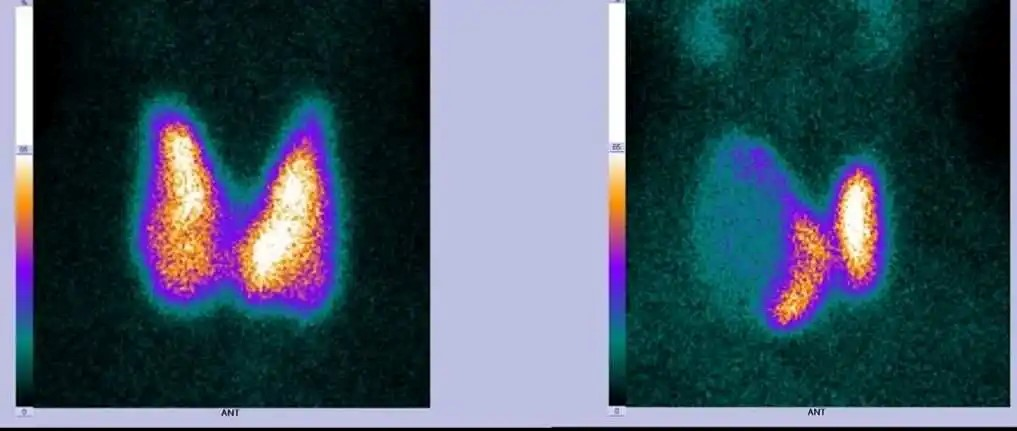

核醫(yī)學(xué)成像:

在核醫(yī)學(xué)診療中,常用的同位素藥物有Tc-99m140keV)、I-131364keV)、F-18511keV)等,基于CdZnTe探測器的伽馬相機(jī),對(duì)射線能量探測范圍廣,幾乎可滿足所有藥物的檢測需求。

CdZnTe探測器能量分辨率、空間分辨率高,單位體積探測效率是NaI2倍以上,檢測準(zhǔn)確性更高,可有效降低病人攝入的放射性藥物劑量。

1732087811161930.png1732087823625839.png